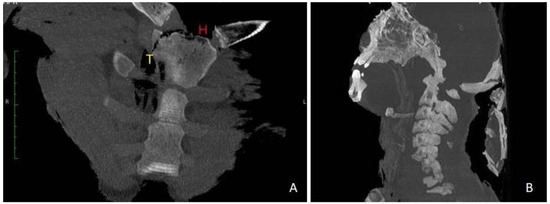

2.3. PMCT Finding

Before the autopsy, PM-CT was carried out on 128-section multidetector CT scanners (Somatom Definition AS, Siemens Healthcare, Erlangen, Germany). The CT protocol consisted of a single total-body acquisition (nominal thickness 0.625 mm, reconstruction thickness 0.625 mm, and 1.25) In case 1, the three-dimensional CT reconstruction showedthe presence of shearing lesions at the level of the third lumbar vertebrae and the disruption of the cortical bone at the vertebral processes (Figure 1). In case 2, total-body CT scan showed multiple fracture rims with clean margins of the neurocranium, upper and lower limb fractures, multi-fragmented fracture of the right zygomatic bone and the nose, and fracture of the sternum; right costal fractures of II, IV, V, VII, and VIII;fracture of the right iliac spine, the right sacral half, the ischial branches, and the pubic bones bilaterally (Figure 2 and Figure 3). PMCT permitted to distinguish traumatic from heat fractures.

Another critical point is the age of the victims. The bones of young people have a different response to heat and blunt trauma than older bones. A recent experimental study showed that younger bone may fragment less than older bone because it can withstand more significant deformation before reaching the fracture point threshold [28]. Even before the autopsy, PMCT can make it possible to differentiate traumatic injuries from heat injuries based on their morphology [13,29,30]. The traumatic bone fractures can be distinguished from heat fractures as they are multifractured and less organized. Heat fractures, on the other hand, show clear margins or clear amputations. Heat fractures of the cranial theca in case 2 were evident: CT scan reported heat fractures as linear and with clear margins.According to literature trans-diploid fractures correspond to the separation of the inner and outer plates of the skull under the action of heat. Moreover, trans-diploid fractures are characterized by the separation of the inner and outer plates of the skull under the action of heat, and by a longitudinal fracture line that crosses the diploe parallel to the cortical bone. Differently, traumatic fractures typically affect both the inner and outer planks and are perpendicular to the bone’s surface.On extensively charred bodies, a complete split between the bone planks is possible, or even the disappearance of the outer bone plank under heat as areas of superficial delamination. Fractures or amputations of long bones have the typical blunt ends described as ‘flute-mouthpiece’ appearance [31,32].

Alongside the case 2 fractures were bony heat amputations of the upper and lower limbs. Heat fractures are thin and linear. If the extremities of the limbs are affected, heat amputations can be observed with regular margins. Such amputations differ from traumatic amputations because they are not covered by soft tissue or skeletal muscle [13]. Furthermore, in some cases, fragmentation can be observed. In our case, PMCT highlighted traumatic fractures involving the eyelid rhyme, sternum, ribs, and pelvic bones. Heat fractures were highlighted at the cranium and the upper and lower limbs.

Figure 2. Case 2. Three-dimensional VR coronal deformatted images made by the dedicated workstation. (A) Burst fracture of the cranial theca. (B,C) Flutemouthpiece of the long bones and thermal delamination of the cortical of the left femur.

Figure 3. Case 2. (A) Paracoronal reformatted MIP-SLAB (20 mm). T: traumatic fracture; H: heat fracture. (B) Sagittal reformatted MIP-SLAB (50 mm). Explosion of the cranial vault.